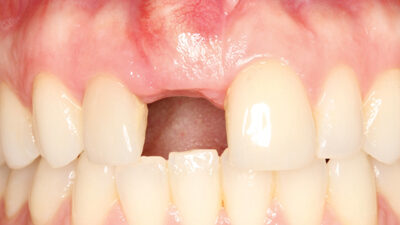

Digital Workflow for Implant Provisionalization in the Aesthetic Zone

Intraoral photo showing frontal view of the patient in MIP with implant healing abutment.

Dental implants have been the recommended treatment of choice as a conservative approach in replacing missing teeth while preserving adjacent tooth structure when compared to fixed dental prostheses.1 The ability of the implant supported crown to replicate natural tooth like emergence profile provides the advantage of achieving higher aesthetic results in the anterior zone.2 Their … Read more